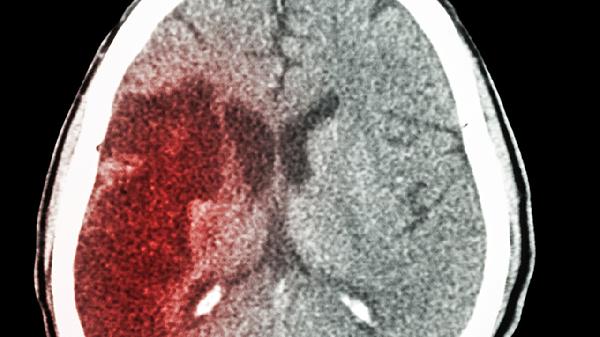

腦室周圍出血或蛛網(wǎng)膜下腔出血后,血塊阻塞腦脊液通路或引起粘連性改變。出血急性期需控制血壓、降低顱內(nèi)壓,慢性期若形成腦積水可考慮腦室腹腔分流術(shù)。頭部CT能明確出血部位及腦室擴(kuò)張程度。